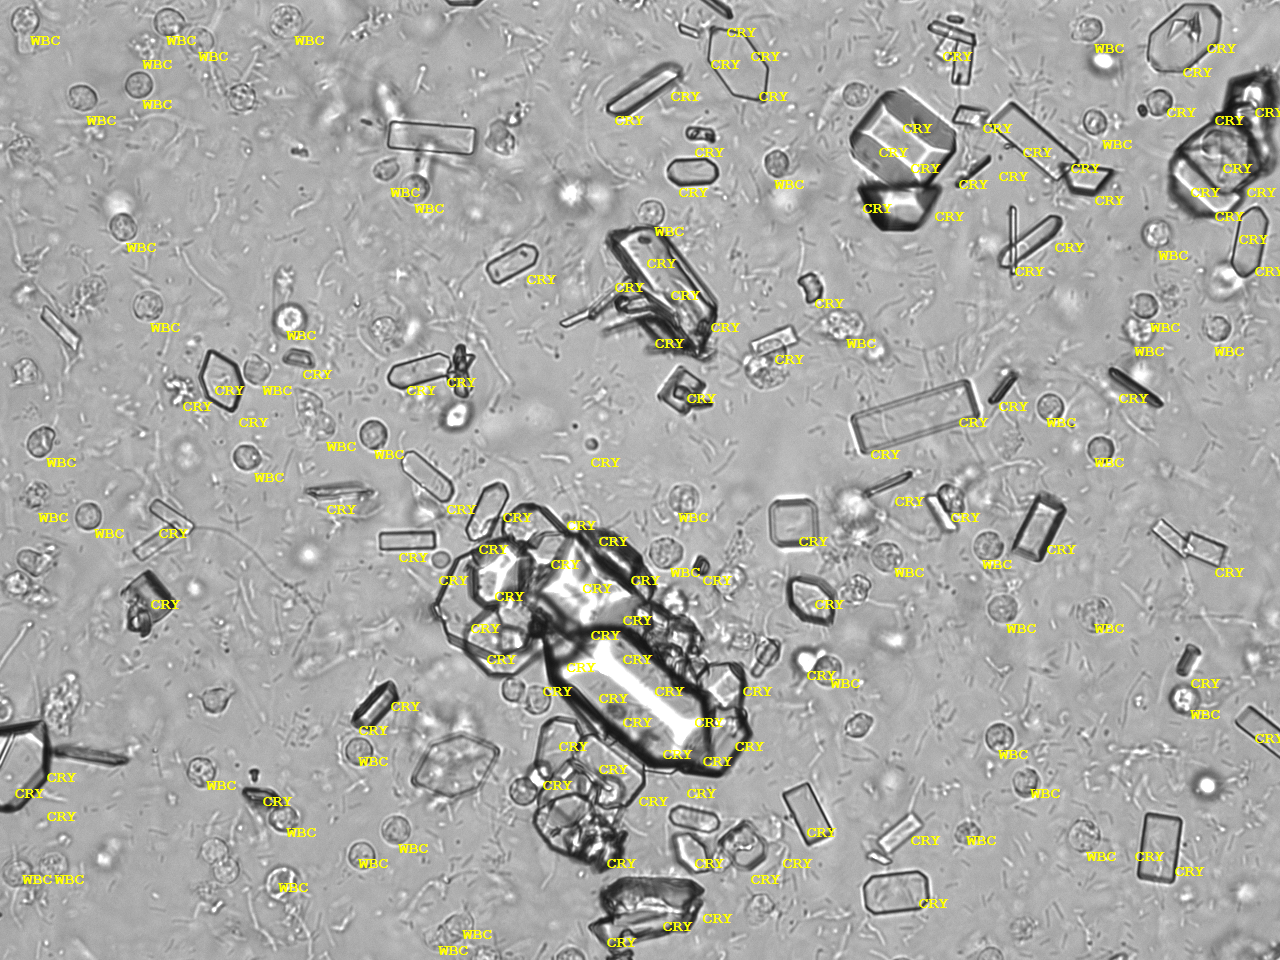

Urin-Feature: Triplephosphate